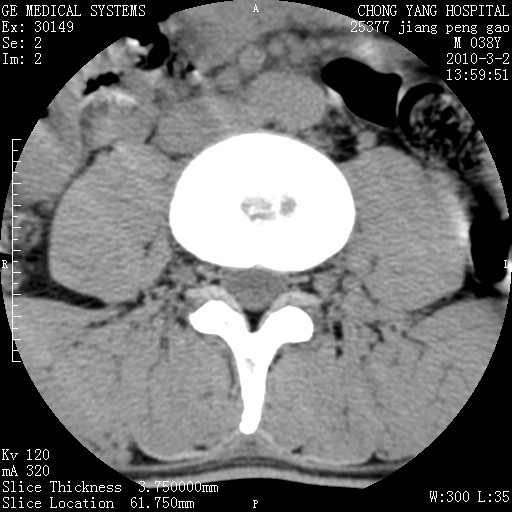

标题: CT24887:M38Y 反复腰痛 无外伤史 未做针灸 竖脊肌为何积气 [打印本页]

标题: CT24887:M38Y 反复腰痛 无外伤史 未做针灸 竖脊肌为何积气

退变,轻度增生/间盘膨出、l5椎后缘软骨结节。

肌间隙积气过多也为退变表现。